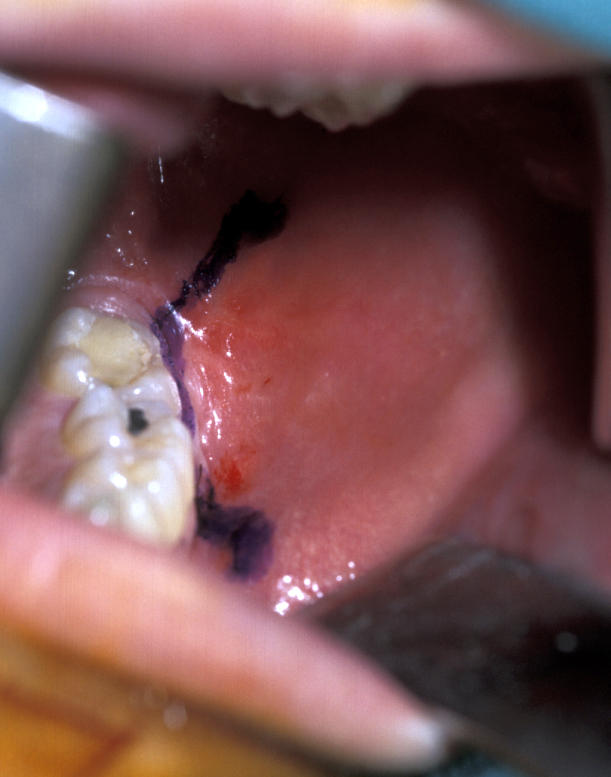

- Palatally placed canines - open eruption can also be used in the treatment of palatally ectopic canines, especially when they are relatively superficial. As the palatal mucosa is all keratinized, the problem of ensuring that the tooth erupts through here is to ensure adequate crown is exposed to ensure that there is no chance of the crown becoming recovered during the healing phase. If necessary, a bracket can be attached at the time of surgery in the same manner as for closed eruption. Care must be taken to ensure that the cementum is not damaged during surgery and that keratinized mucosa is left overlying the cementum - enamel junction. Interestingly even if large areas of bone are left denuded after surgery healing is usually excellent and uneventful. Packs can be placed over the exposed tooth to aid haemostasis, comfort and to prevent the tooth becoming covered again. This has historically involved the placing of ribbon gauze soaked in varnish and secured in place with mattress type sutures. Periodontal dressing can also be used. The pack should be removed after 7 to 14 days, from when on vigorous oral hygiene measures are vital to encourage healing, prevent gingival overgrowth and encourage eruption (Figure 19 and Figure 20).